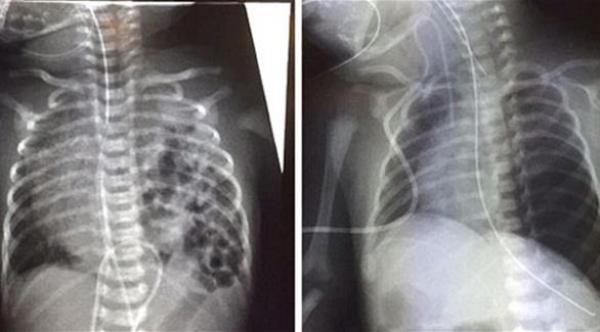

وعقب ولادة الطفلة بيني، كانت تملك نصف رئة تعمل، ولم تكن قادرة على التنفس، وظلت لفترة طويلة في العناية المركزة بالجهاز التنفسي الصناعي، وأجرت الطفلة عملية جراحية خطيرة لإزالة أعضاء البطن المستقرة في الصدر وإرجاعها إلى مكانها الطبيعي، وسد الثقب، ونجحت العملية بمعجزة، وبدأت الرئة تعمل بشكل طبيعي وأصبح بإمكان الوالدين اصطحاب طفلتهما إلى المنزل.